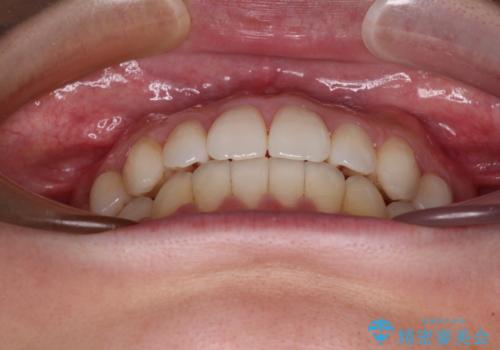

インビザラインで口を閉じやすく

- 下唇に上の前歯が当たることを気にして来院された患者様です。

上顎の親知らずを抜去し、歯列全体を後方に移動させるとともに、IPR(歯と歯の間を削る)を行うことで口元の閉じにくさを改善していくこととしました。

咬合力が強く、マウスピースを介した咬み込みが顕著であったため、奥歯の咬みにくさやIPRのスペースが改善しにくく、治療期間が思った以上にかかってしまいました。